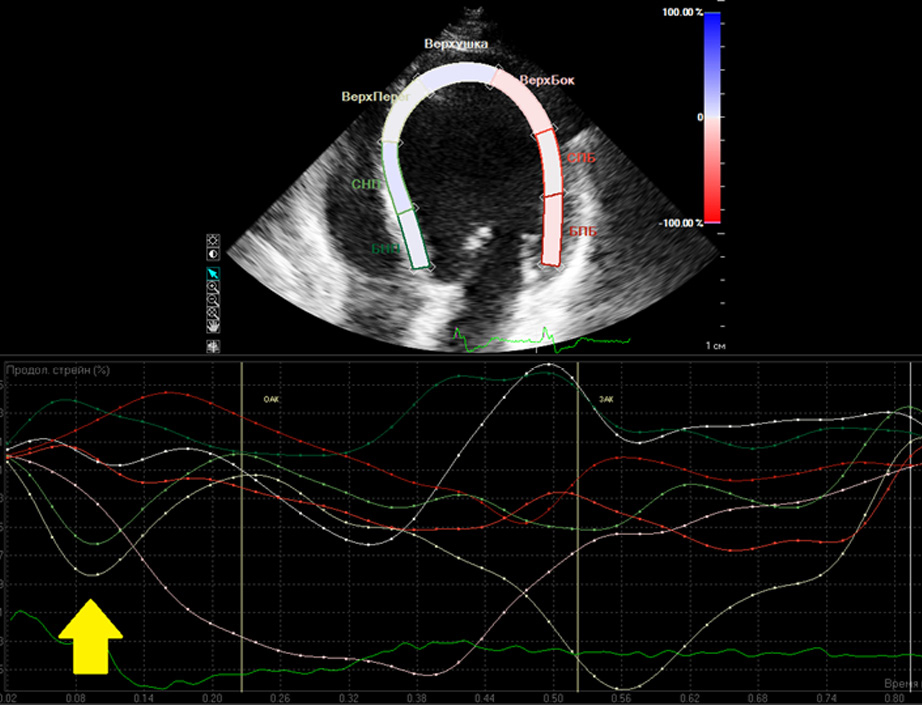

Преждевременное проведение ЭИ при пБЛНПГ от ПЖ через МЖП может сопровождаться изменением транссептального градиента давления. В ряде случаев этот процесс сопровождается формированием SF – ранним сокращением МЖП в течение 70% фазы изгнания ЛЖ [4] (рисунок 1). Согласно результатам нашего исследования, по данным обеих методик – STE и TDI – наличие SF подтверждается преждевременным наступлением пика LS в базальном сегменте МЖП.

Рисунок 1. Раннее пресистолическое наступление пика LS базального и среднего сегментов МЖП у пациента с наличием SF (указано стрелкой).